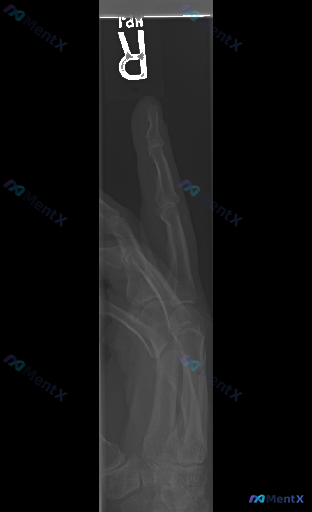

X光报告写着"未见明显异常",但临床提示存在异常?这个右手影像的下一步思路怎么走

前提是:临床明确提示“存在异常”,但这份右手斜位X光的“基础版报告”写着——

- 骨皮质连续,未见明显骨折线/脱位

- 骨质密度、骨小梁大致正常

- 关节间隙尚可,无明显骨赘/侵蚀

- 软组织边界清,无广泛肿胀/气肿

但结合“存在异常”的这个大前提,再看同一张片子,大家觉得下一步应该优先从哪里切入?

或者说,哪些“看不见的异常”是我们必须保持警惕的?